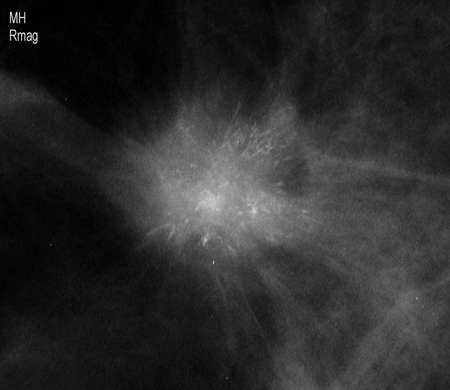

Magnification view demonstrating irregular spiculated mass with associated calcifications

Courtesy of Dr Nancy Pile, University of Louisville; used with permission